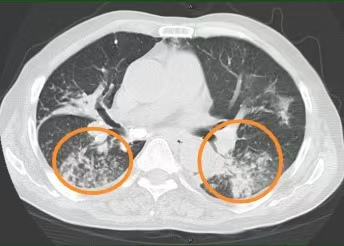

入院后,医生给王大爷用了抗感染、止咳化痰、营养支持等治疗,可3天过去,王大爷喘息、气促、咳嗽、咯黄痰仍没缓解,胸壁包块也没缩小,包块局部触摸还有波动感。复查胸部CT提示:双肺多发结节影、磨玻璃影、斑片影,部分见肺实变影,部分支气管牵拉扩张,左肺下叶部分支气管闭塞。